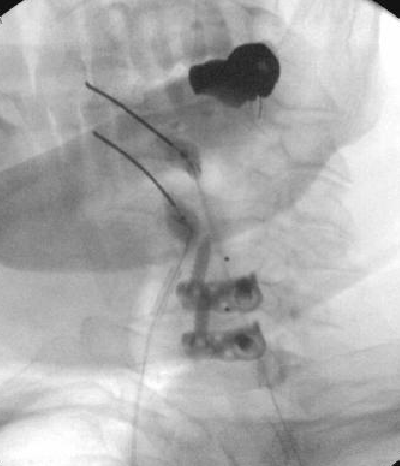

Haha he was wondering if worsening stenosis or listhesis was an issue, thought the slip might need surgery with axial pain. Just showing a bad slip, can still be treated with good results, don't forget about endplates.Basically Rolo’s saying don’t worry about it but look at what I did 😆

I know I was just messin 😉Haha he was wondering if worsening stenosis or listhesis was an issue, thought the slip might need surgery with axial pain. Just showing a bad slip, can still be treated with good results, don't forget about endplates.

This is now off-topic but - What is your general experience with Intracept for stable spondylolisthesis? Was this guy presenting as a typical "anterior column" pain? Or was it non-specific and he happened to have Modic? I have a 30 year old with history of scoliosis and surgery from L2 up, who has old pars fractures at L5 with stable spondy at L5-S1 and type 1 Modic. Failed MB RFA and ESI. All axial pain with occasional left leg pain but axial is main complaint. His symptoms are fairly non-specific, but he's a normal guy. Hesitant to offer Intracept, but absolutely do not want to send him for a fusion since he's already fused at L2 and I think it will just be a cascade.Haha he was wondering if worsening stenosis or listhesis was an issue, thought the slip might need surgery with axial pain. Just showing a bad slip, can still be treated with good results, don't forget about endplates.

No hesitation with stable spondy. Even if there's a few mm movement on flex ext but radicular component is mild/intermittent, I still do, just tell them they may have higher chance of radiculitis, though I haven't seen that to be the case. Outcomes still mirror literature.This is now off-topic but - What is your general experience with Intracept for stable spondylolisthesis?

Pain was more "always there", worse with activity, morning stiffness, transitioning from different positionsWas this guy presenting as a typical "anterior column" pain?

I think he's a good candidate. Young people with Modic 1 usually do well, especially since you've ruled out other causesOr was it non-specific and he happened to have Modic? I have a 30 year old with history of scoliosis and surgery from L2 up, who has old pars fractures at L5 with stable spondy at L5-S1 and type 1 Modic. Failed MB RFA and ESI. All axial pain with occasional left leg pain but axial is main complaint. His symptoms are fairly non-specific, but he's a normal guy. Hesitant to offer Intracept, but absolutely do not want to send him for a fusion since he's already fused at L2 and I think it will just be a cascade.